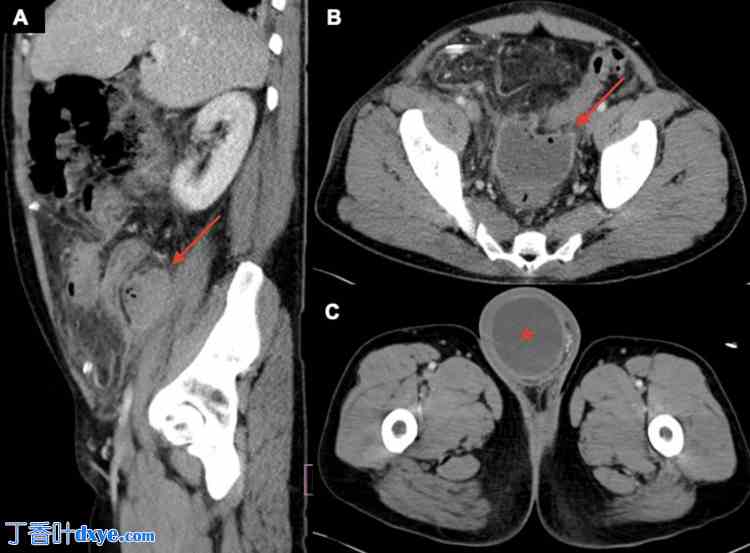

患者开始静脉注射哌拉西林-他唑巴坦进行经验性抗生素治疗,并请普外科会诊。患者接受了腹腔镜阑尾切除术,结果显示化脓性腹膜炎和坏死阑尾突入腹股沟疝囊,周围有大量脓液。疝囊内的大网膜完整,易于复位至腹腔。鉴于该患者阑尾破裂伴有大面积化脓和炎症,医生决定在右下腹放置杰克逊-普拉特(Jackson-Pratt,JP)引流管,并根据分期手术推迟疝修补术。术后第7天,患者出现明显的弥漫性腹痛和腹胀,白细胞增多至18.84 × 103个/µL,且进一步恶化。血培养结果为阴性。再次进行腹部和盆腔CT扫描,并经口服静脉和静脉注射造影剂,结果显示右腰大肌前方有一3.5 x 4.9厘米的脓肿,下盆腔直肠前方有一4.4 x 6.6厘米的深盆腔脓肿,液体通过未闭的腹股沟管延伸至阴囊(图3)。

图 3. 腹部和盆腔的矢状面 (A) 和轴向 (B 和 C) CT 图像,经口服和静脉注射造影剂后显示一个 3.5 x 4.9 cm 的右腰大肌脓肿(A,红色箭头),一个 4.4 x 6.6 cm 深的盆腔脓肿(B,红色箭头),以及通过开放的腹股沟管延伸到阴囊的液体,提示为脓肿而非反应性鞘膜积液(C,红色星号)。

CT:计算机断层扫描